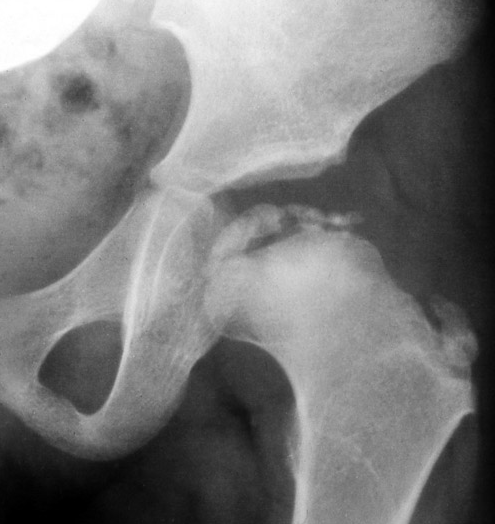

Avascular Necrosis (AVN) Aseptic Necrosis or Osteonecrosis

Avascular necrosis (AVN) has been called by many other names: aseptic necrosis, osteonecrosis, bone infarction and even bone “infraction.” AVN is a condition in which the blood flow to a region of bone becomes impaired. This then results in bone cell death (necrosis).